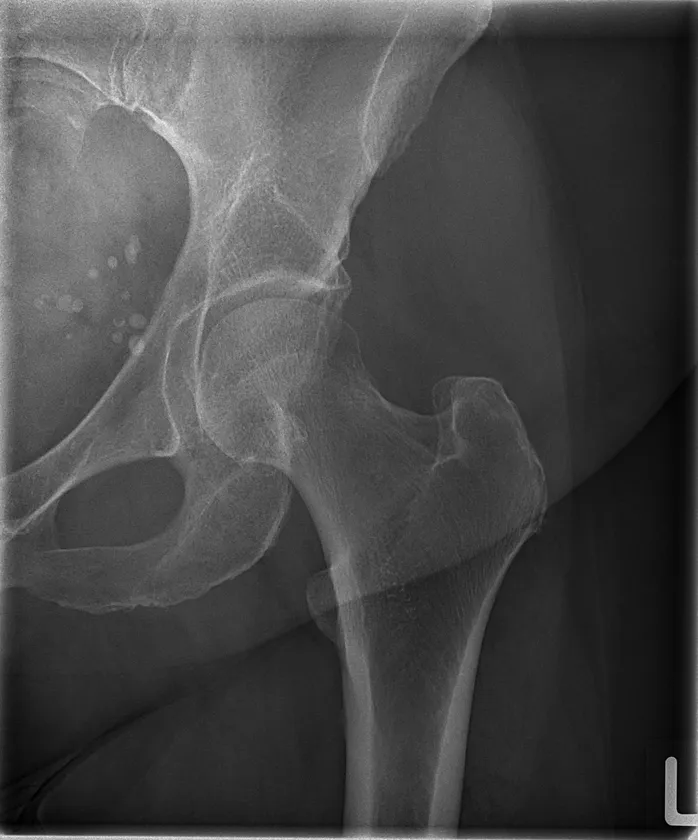

TRB 9020Hで撮影した大腿骨レントゲン写真

※84 kV HP mode 1.8 mAs, 0.12 sec Exposure Index: 367